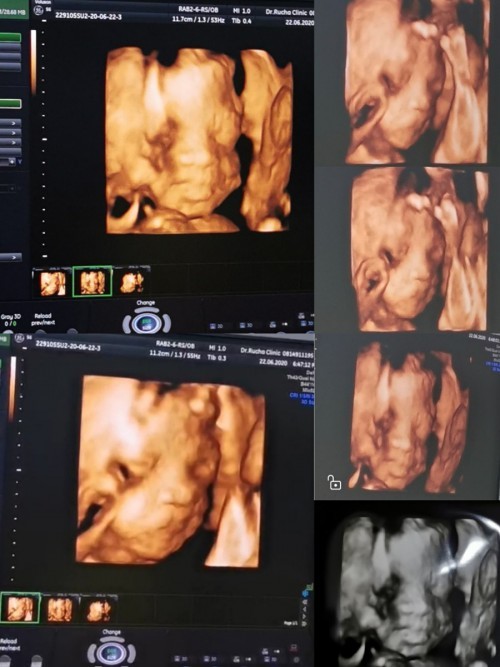

แม่ซาว4มิติดูหน้าลูกกันตอนกี่วีคคะ 20วีคจะเห็นหน้าน้องชัดไหมคะ ขอบคุณคะ🥰

ซาวด์ตอน26wค่ะ เห็นชัดเลยค่ะ

ตอน22 สัปดาห์ค่ะ